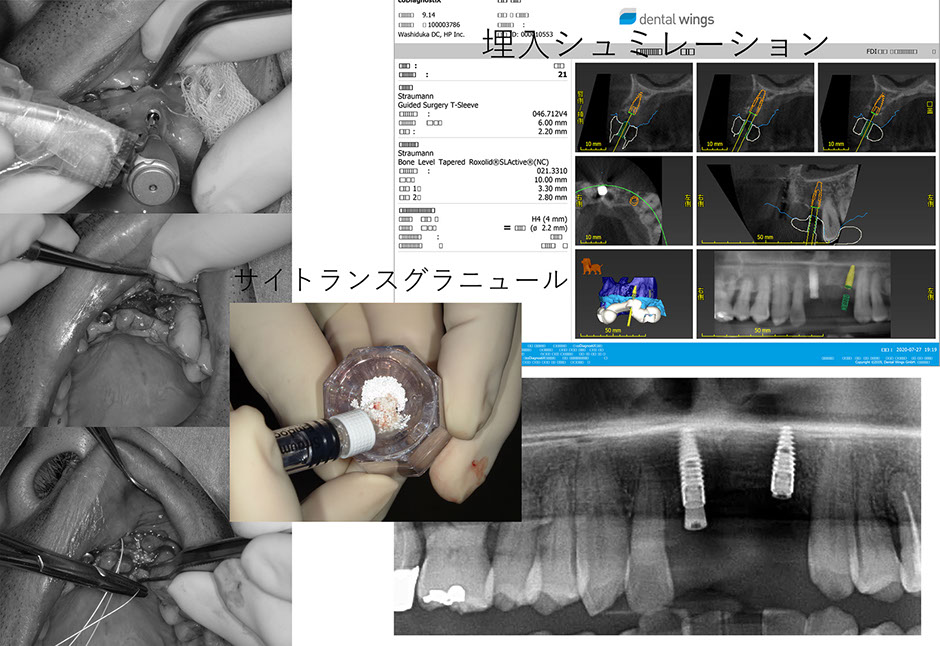

当院のインプラント治療はデジタルCTデータを基に専用ソフトにてインプラント手術をシミュレーションし、手術から最終補綴まで安心、安全そして長期安定性を目指し最新のプロトコルによるデジタルシステムで対応しています。また、骨の状態により骨増生、サイナスリフト、ソケットリフト、ボーンスプレッディング等、様々な対応をいたします。

当院で使用している骨補てん材は人体の骨と同じ成分の「炭酸アパタイト」が主成分で、患者さん自身の骨に緩やかに置換されます。国内では初めてインプラント埋入時での併用が認められましたsee more